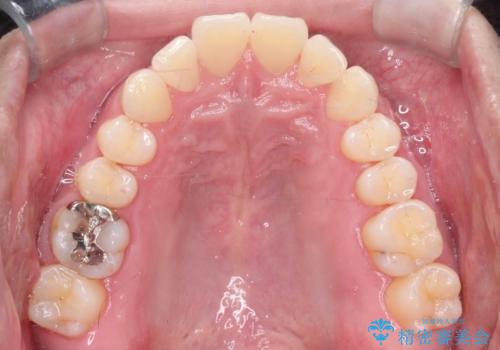

- 前歯の凸凹と顎の偏位を主訴に来院されました。

下顎の偏位を認めましたが、外科矯正を希望されなかったためできる範囲で顎の偏位を治すことができるよう治療を行なっております。

治療開始前に、下顎位の評価をおこなうことで、完成度の高い治療を行うことができました。